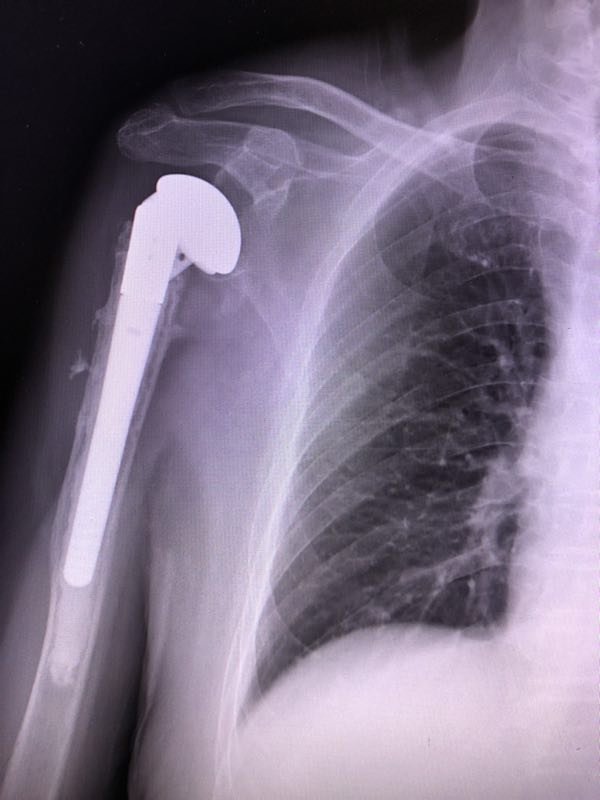

人工肱骨头置换术